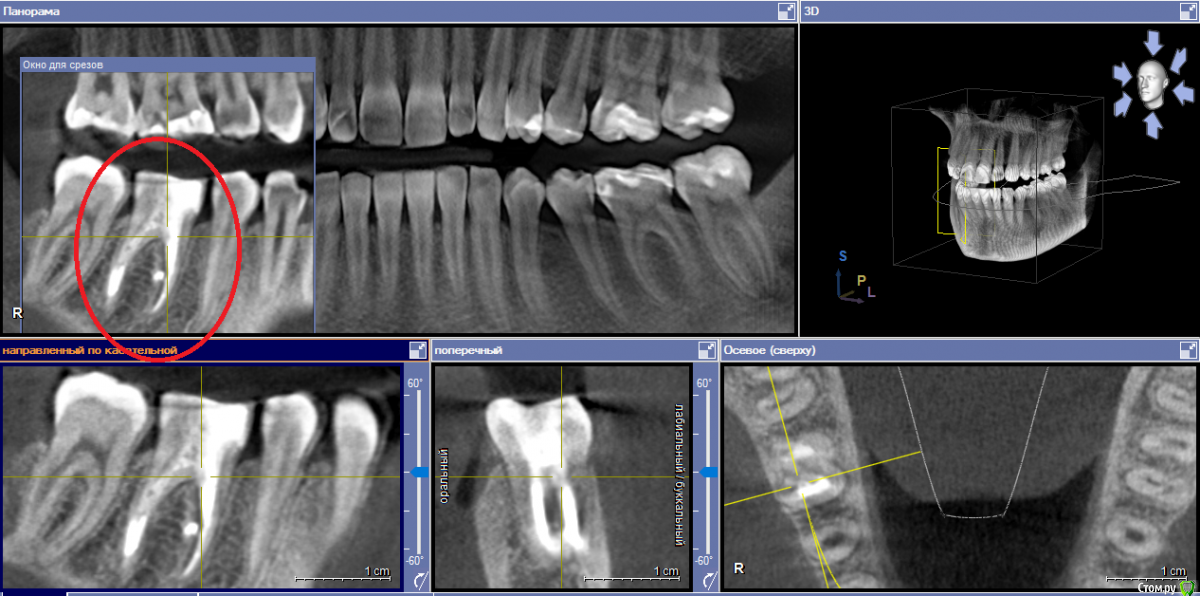

yellowborodova Опубликовано 5 января, 2020 Автор Поделиться Опубликовано 5 января, 2020 Здравствуйте... всех с праздником)) прошу прощения, что так долго... вот срезы кт и панорама. Надеюсь, заскринила то, что нужно)) буду рада, если у кого-либо будет желание и возможность прокомментировать тему. Ссылка на комментарий

yellowborodova Опубликовано 5 января, 2020 Автор Поделиться Опубликовано 5 января, 2020 Ссылка на комментарий